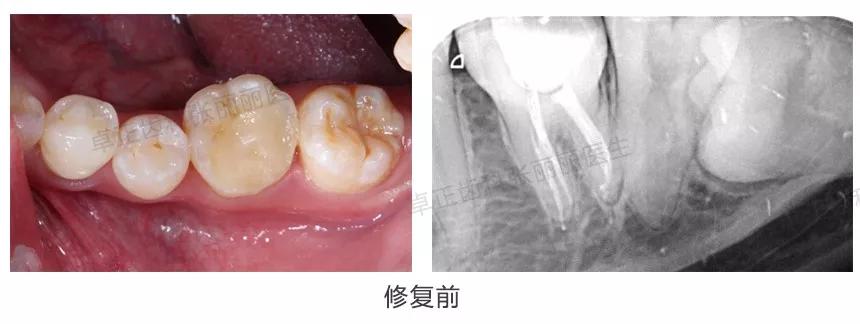

▍ 全冠

当后牙缺损较大,特别是根管治疗后,由于后牙较大的咬合力通过开髓洞口产生的楔力,非常容易导致牙齿劈裂,因此建议全冠修复。参考《根管治疗后的牙齿为什么通常需要做冠》。

临床案例:左上第一前磨牙因龋坏行根管治疗,进行全冠修复。

▍ 高嵌体(部分冠)

由于全冠修复需要磨除较多牙体组织,对于一些根管治疗后缺损范围不太大的后牙,为了尽量保存牙体组织,也可以采用覆盖全部面的高嵌体(部分冠)修复。

临床案例:左下6根管治疗后,采用覆盖全部面的高嵌体修复,相比全冠修复,牙体预备量减少。